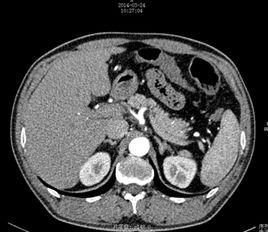

病理

①主要是單個腺瘤(70%~80%)。

②腎上腺皮質增生占20%~30%,其中雙側增生多見,又稱特發性醛固酮增多症;少數增生患者的臨床表現及生化改變可被小劑量地塞米松所抑制,故被稱為促腎上腺皮質激素(ACTH)依賴性或地塞米松可抑制性醛固酮增多症;還有一種單側或雙側增生患者的生化改變類似於腺瘤,被稱為原發性腎上腺皮質增生症。